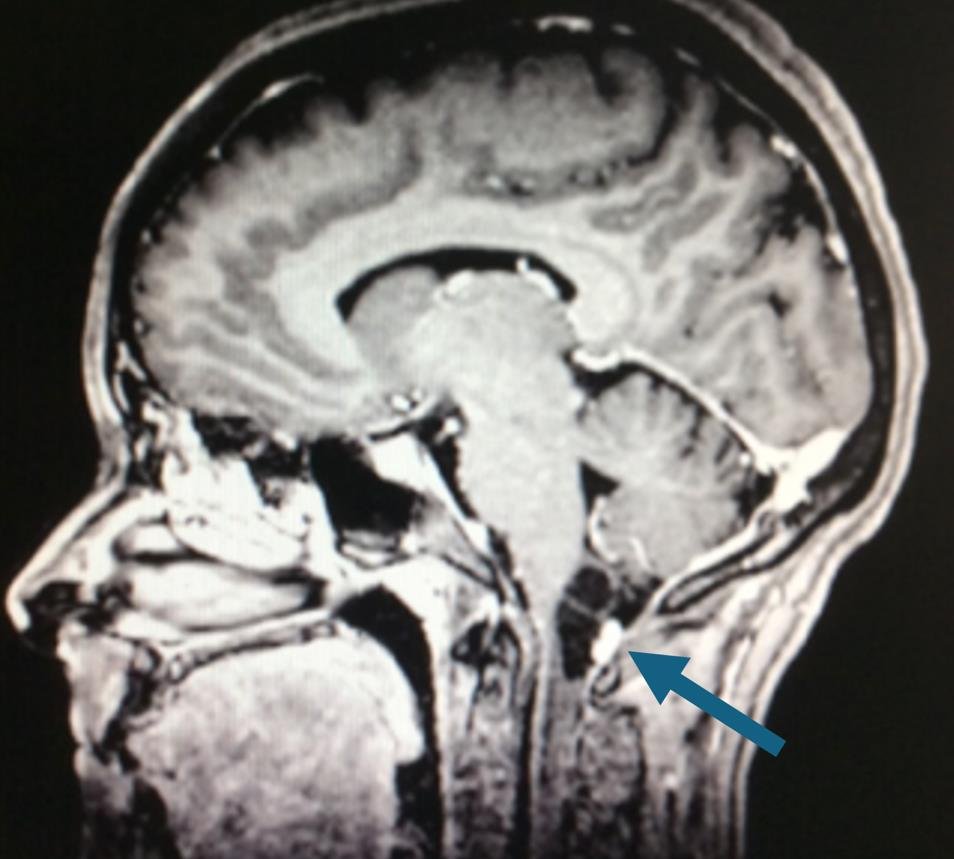

Prueba de elección para tumores de columna y médula espinal. Evalúa partes blandas, relación con la médula y raíces, y detecta compresión, edema, necrosis o hemorragia intratumoral.

Diagnóstico de los Tumores Vertebrales y Medulares

El diagnóstico se basa en: